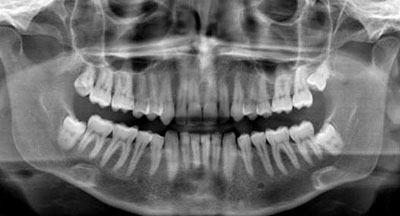

Врач назначает анализы, рентген или компьютерную томографию зубов. Рентгенография отображает, насколько разрушены межзубные перегородки. Томография даёт трёхмерное изображение костной структуры.